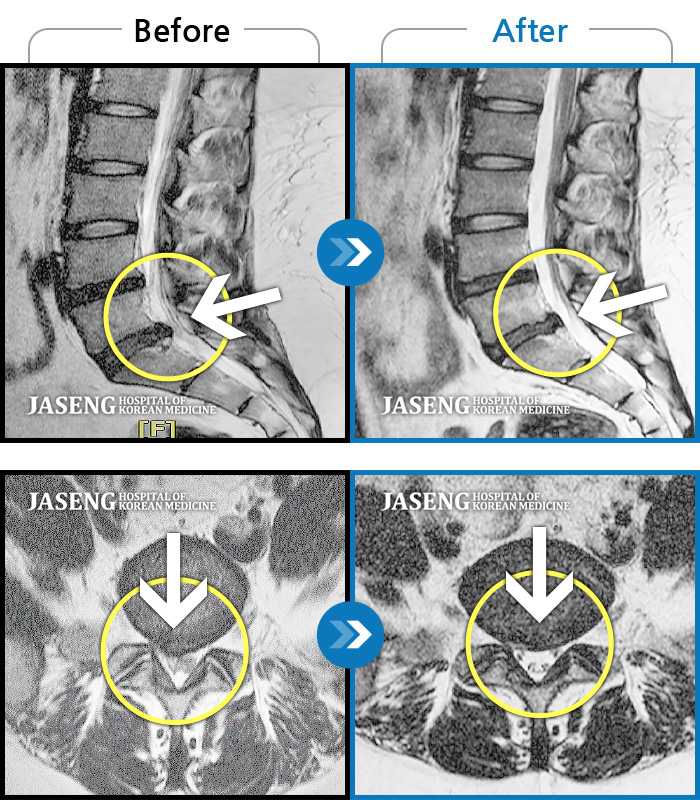

목디스크

도움받은 사례

인천 · 강아현 원장

좌측 목 통증 및 견갑내연 통증, 팔 전체 통증으로 일상생활에 어려움을 겪는 상태로 내원하셨습니다.

촬영시기

2023.11.27 ~ 2024.05.27

2024.06.03

조회수 481